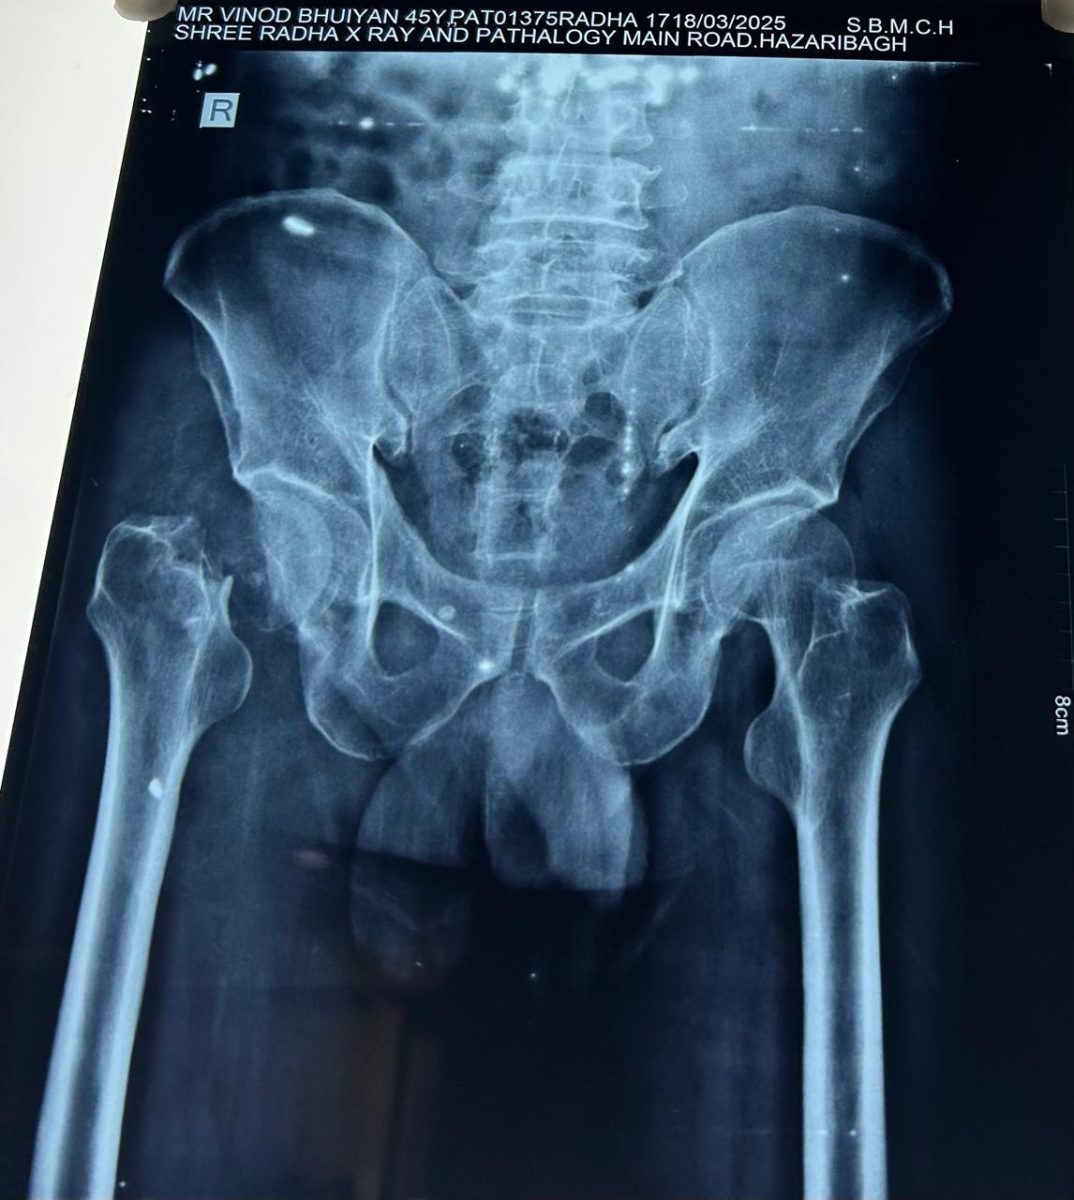

45-year-old male, sustained a fall from stairs over a month prior to presentation. He was initially managed conservatively at a local clinic, but experienced persistent hip pain, an inability to bear weight, and increasing difficulty performing daily activities. On evaluation at our center, clinical examination revealed limb shortening, tenderness, and restricted range of motion. Radiographs confirmed an old, displaced fracture of the femoral neck with no evidence of healing.

Given the duration and non-union of the fracture, combined with the patient’s age and desire to resume an active lifestyle, uncemented total hip replacement was recommended.